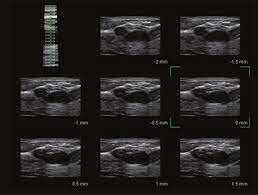

Toshiba Xario™ XG je barevný ultrazvukový systém se sdílenými službami Doppler, který kombinuje vynikající kvalitu obrazu s ergonomickým designem. Tento všestranný přístroj je vybaven řadou pokročilých funkcí, které zajišťují konzistentní poskytování vysoce kvalitních snímků v širokém spektru klinických aplikací, včetně břicha, prsou, malých částí, štítné žlázy a specializovaných OB/GYN aplikací s 3D/4D zobrazením.

- Všestranné použití: Aplikace pro břicho, prsa, malé části, štítnou žlázu a OB/GYN.

- Vynikající kvalita obrazu: Detailní a jasné zobrazení pro přesnou diagnostiku.

- ApliPure™: Technologie pro vynikající čistotu a detaily obrazu ve všech režimech.